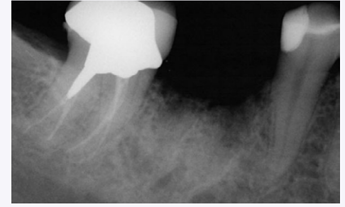

Periapical radiograph taken 3 months post-socket augmentation.

The site was covered with a collagen fleece (Fig. 5). Over a 3-month period, the patient was monitored for soft tissue healing and radiographic evidence of graft resorption and bone formation. A radiograph was taken which revealed a defect fill (Fig. 6).